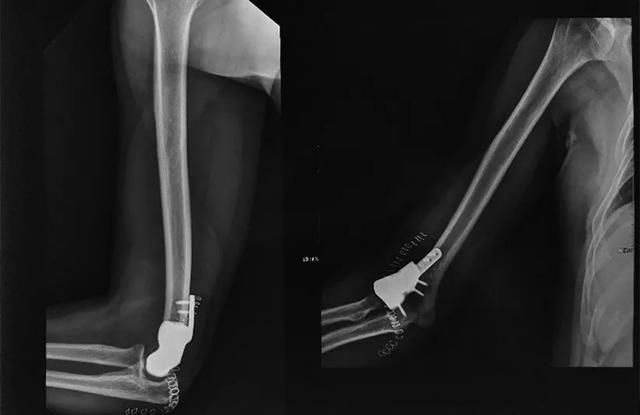

术前影像表现

据介绍,患者因右肘外侧疼痛就诊于烟台山医院骨病与骨肿瘤科,门诊拍片发现右肱骨远端骨质破坏,经追问病史发现曾因肾癌做过肾切除术,后被诊断为右肱骨远端肾癌骨转移,并收入院。